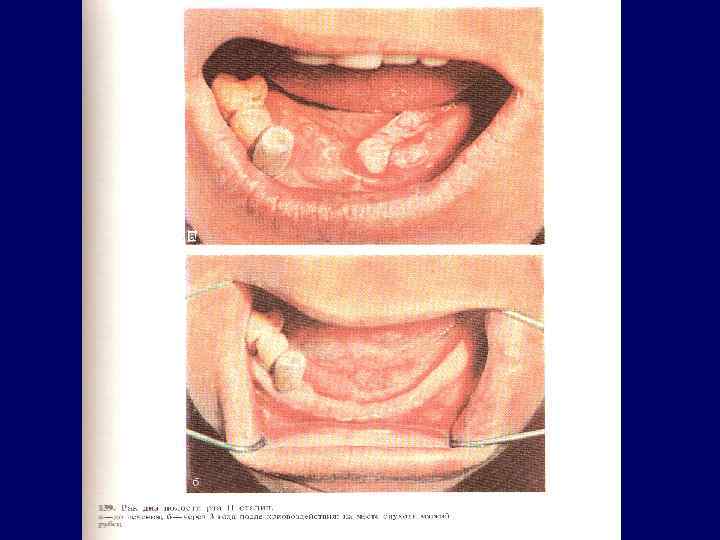

Рак дна полости рта Особенности течения рака дна полости рта идентичны течению рака языка Язвенно-инфильтративная форма Быстро метастазирует в регионарные лимфатические узлы

Рак дна полости рта Особенности течения рака дна полости рта идентичны течению рака языка Язвенно-инфильтративная форма Быстро метастазирует в регионарные лимфатические узлы

Рак дна полости рта с переходом на язык

Рак дна полости рта с переходом на язык